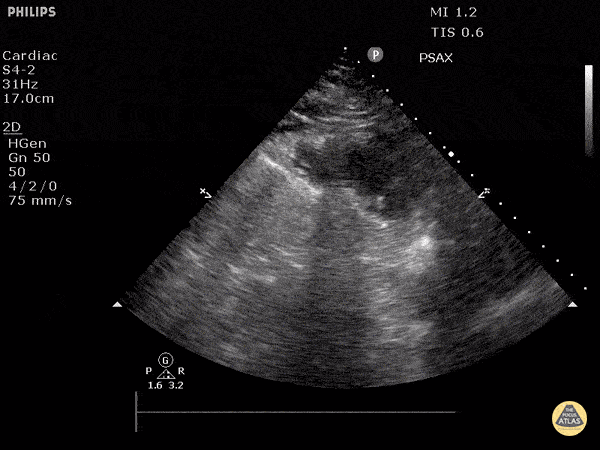

Left Ventricular Dysfunction - Hyperdynamic Left Ventricle (Short)